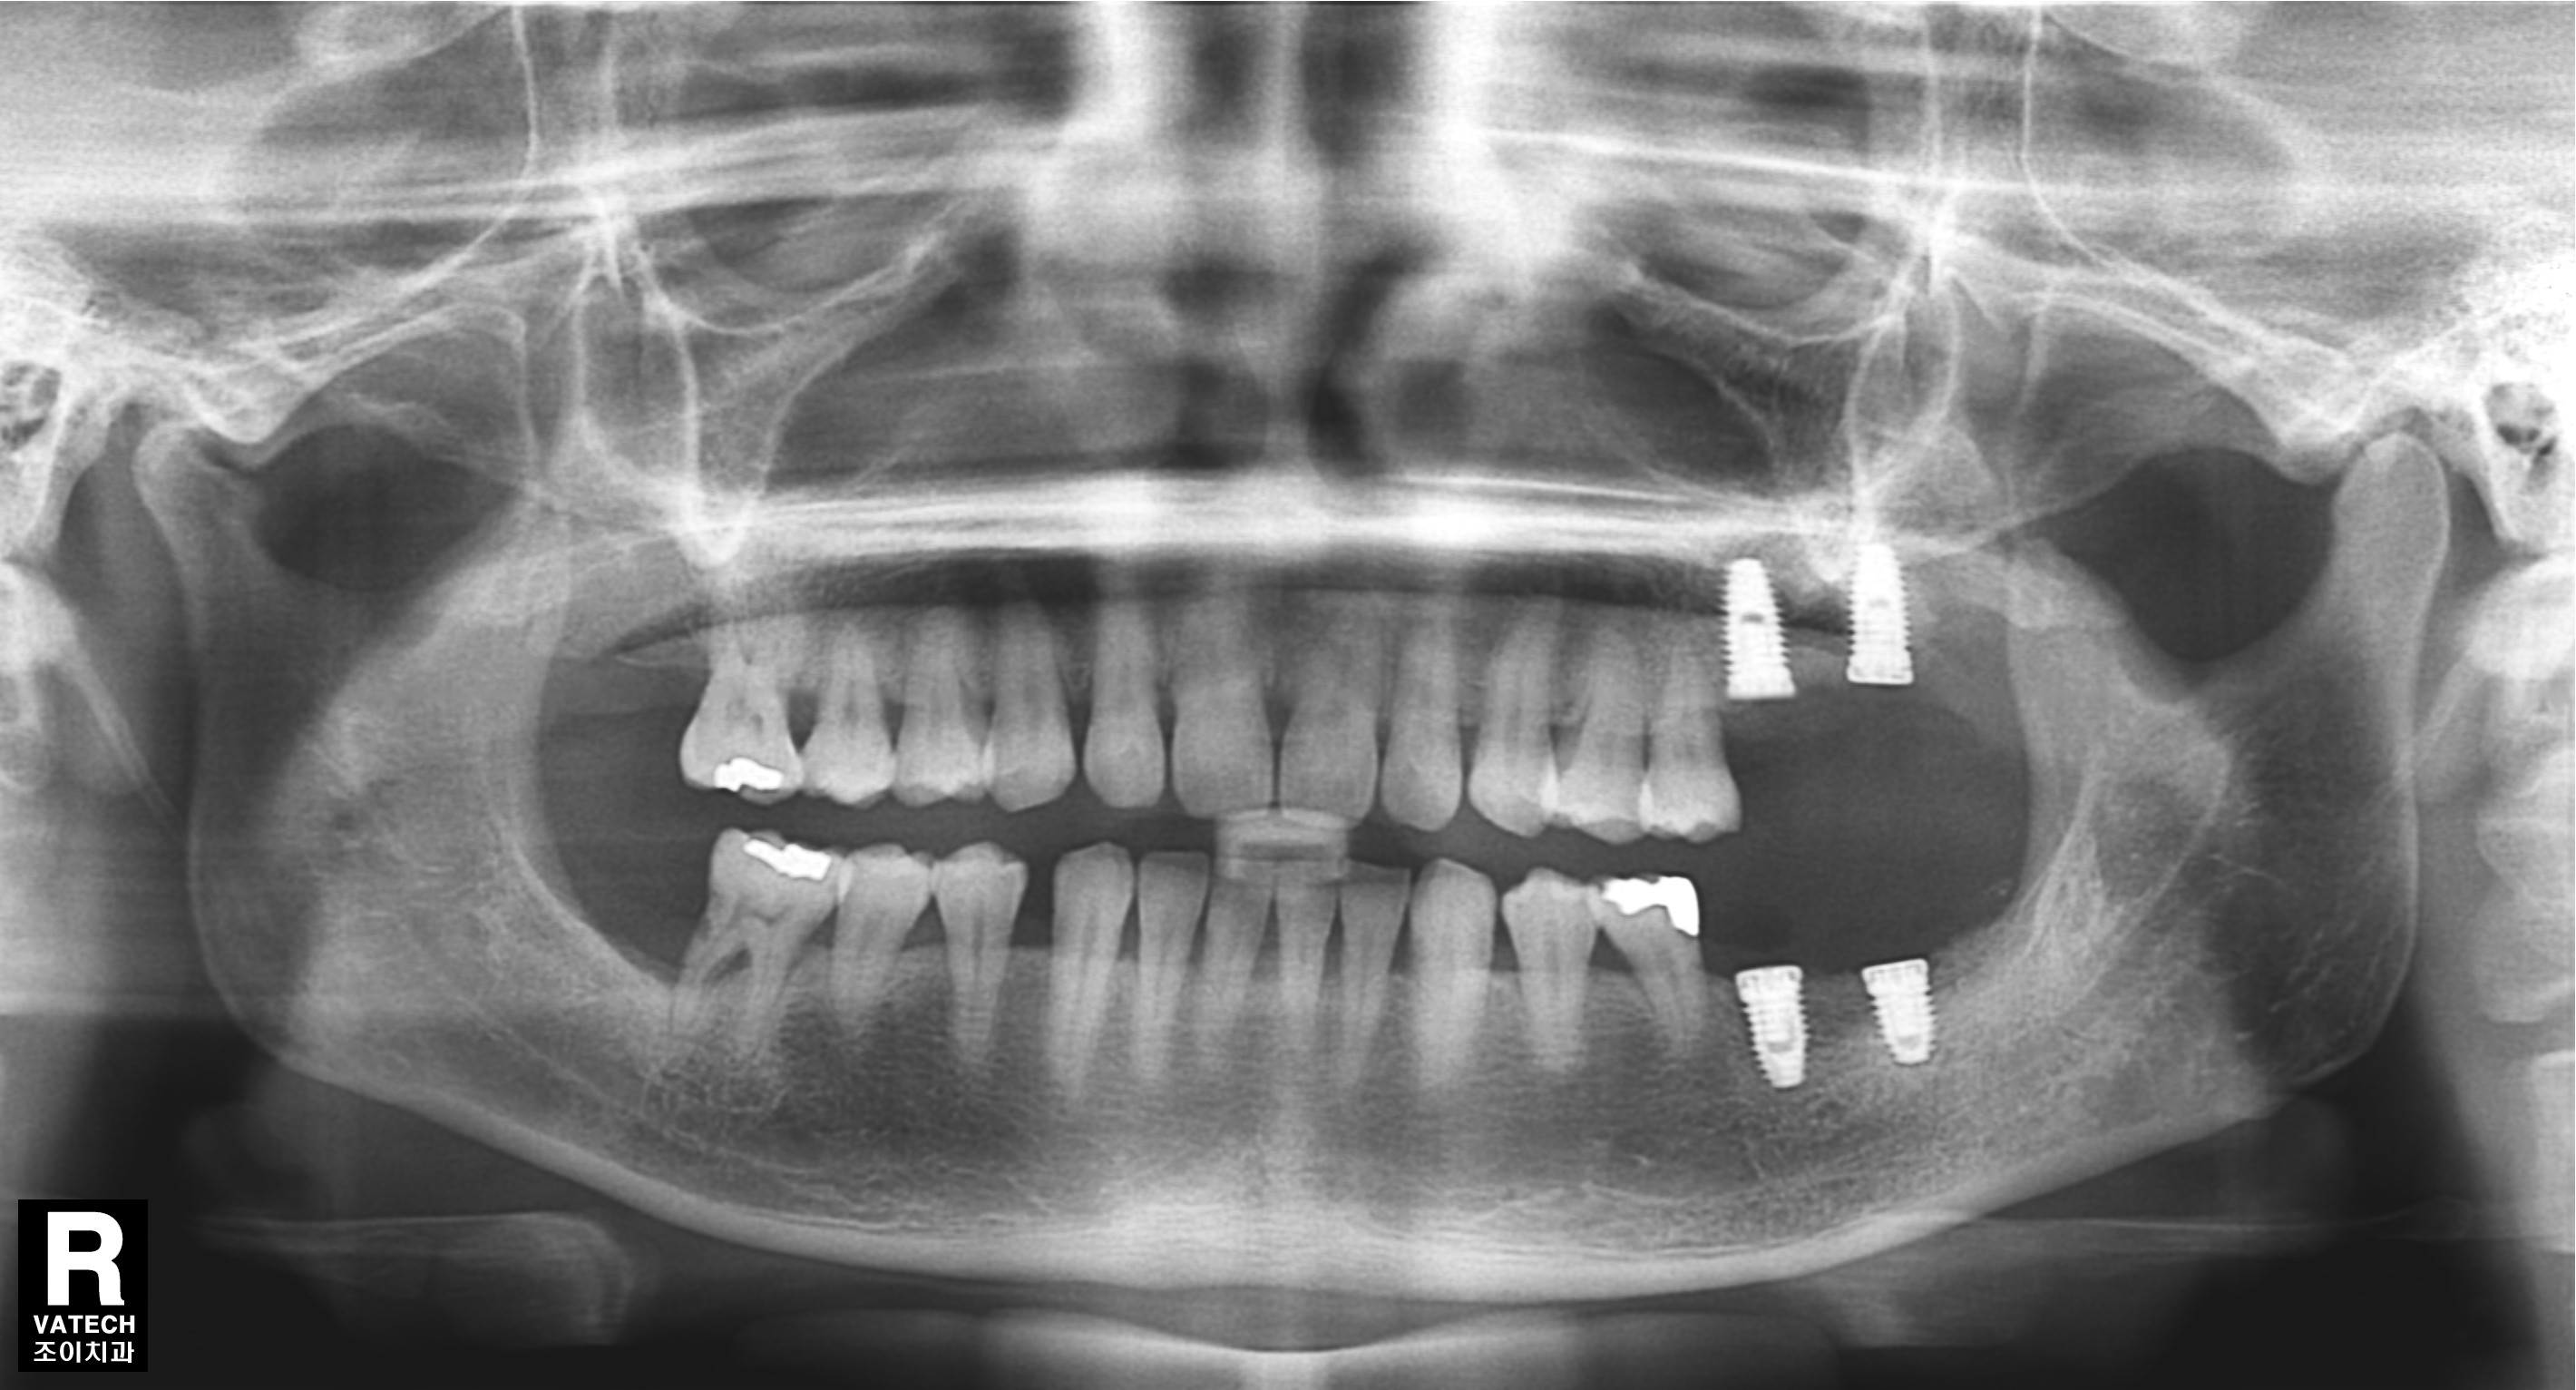

치주질환으로 치조골이 많이 녹아 내려간 경우 원하는 위치에 바로 임플란트를 심을 수 없는 경우가 많습니다.

또한 임플란트의 실패율도 높아집니다.

이 경우 골을 이식하는 것을 먼저 하고 수개월이 경과한 후에 다시 임플란트를 심어야 합니다.

그래야 원하는 위치에 임플란트를 심을 수 있고, 성공율을 높이며, 장기간 문제 없이 잘 유지할 수 있습니다.